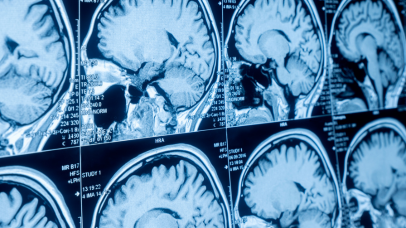

Journal of Commissure is a peer-reviewed publication dedicated to advancing the field of neurology through high-quality research and clinical studies. Established in 2024, our journal serves as a vital resource for neurologists, neuroscientists, and healthcare professionals worldwide.

Neuroimaging, Neuropathology vnmishraneuro@bhu.ac.inSubscribe to our newsletter